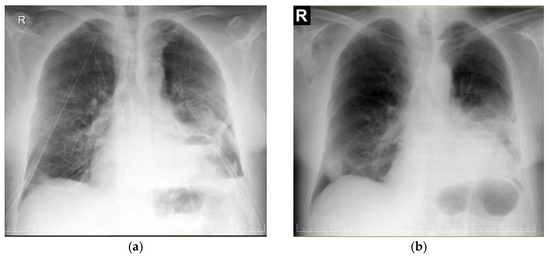

| CRC 1 (minimal compression) |

|

| CRC 2 (moderate compression) |

| CRC 3 (“giant mediastinal tumor”) | |

| CRC 3A |

| CRC 3B |